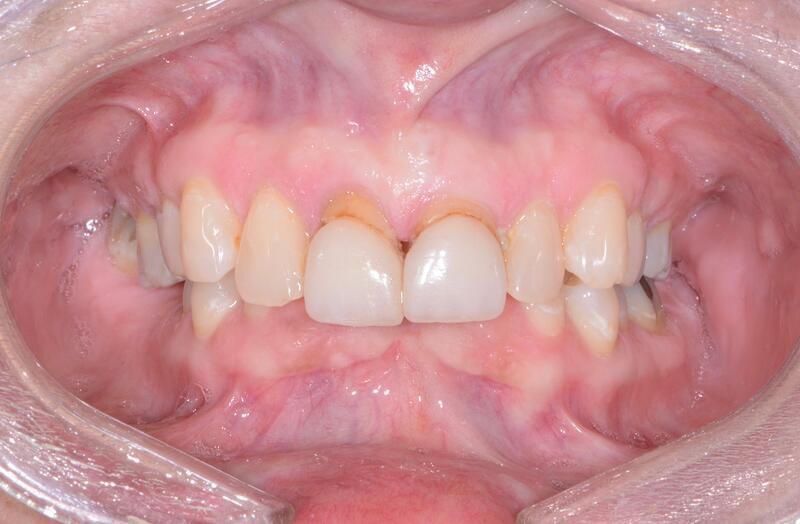

口內(nèi)戴牙照片